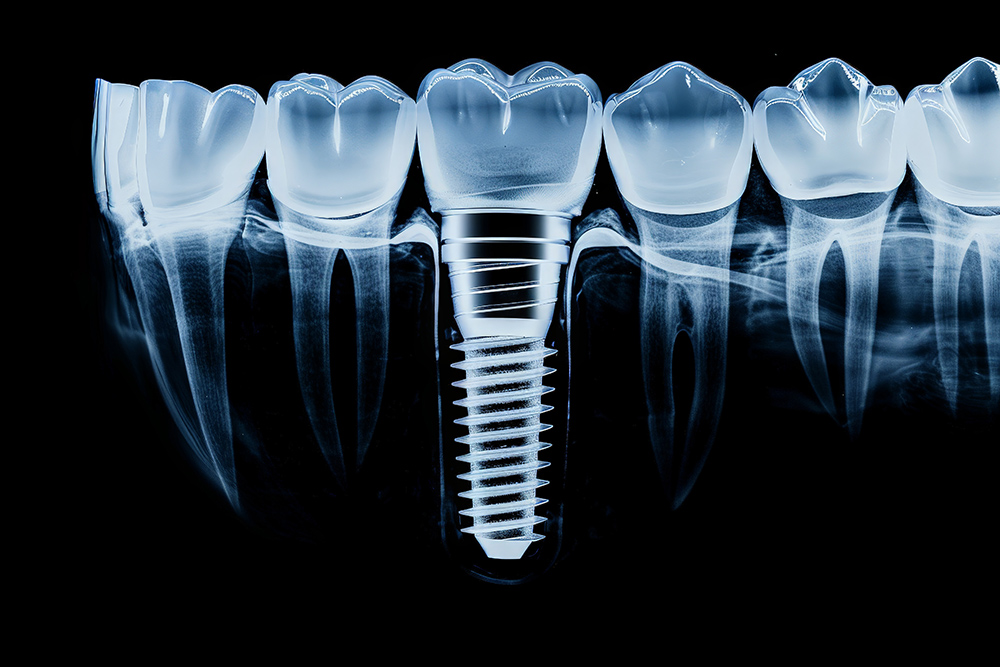

임플란트 치료기간은 다양한 요인에 의해 영향을 많이 받고 있습니다. 첫째, 개인의 건강 상태가 큰 영향을 미칩니다. 만성 질환을 앓고 있거나 면역력이 약한 경우, 회복 속도가 느려질 수 있습니다.

둘째, 구강 건강 상태도 중요한 요소입니다. 잇몸 질환이나 뼈 손실이 있는 경우, 추가 치료가 필요할 수 있으며, 이로 인해 치료기간이 길어질 수 있습니다.

셋째, 사용되는 임플란트의 종류와 치료방법에 따라 기간이 다를 수 있습니다. 예를 들어, 즉시 부하 임플란트는 일반 임플란트보다 빠르게 완료될 수 있지만, 모든 환자에게 적합한 것은 아닙니다.

네 번째로, 환자의 생활 습관도 중요한 역할을 합니다. 흡연이나 과도한 음주 등은 치유 과정을 방해할 수 있으며, 이로 인해 치료기간이 연장될 수 있습니다. 마지막으로, 담당하는 치과의사의 경험과 기술 수준도 영향을 미칩니다. 숙련된 치과의사는 보다 효율적으로 시술을 진행할 수 있으며, 이는 치료기간 단축에 도움이 될 수 있습니다.